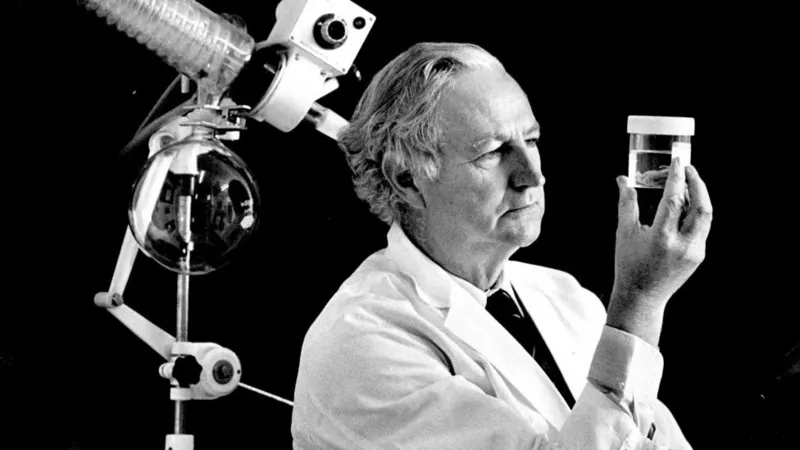

El doctor William McBride, desde Australia, fue uno de los primeros médicos que alertó sobre los peligros de la talidomida en 1961.

La Asociación Médica de EE.UU. analizó la talidomida y sus efectos. En esta foto, el doctor Samuel Andelman, comisionado de Salud de Chicago en 1960, mostraba algunas de las pastillas recuperadas por el Departamento de Salud de EE.UU.